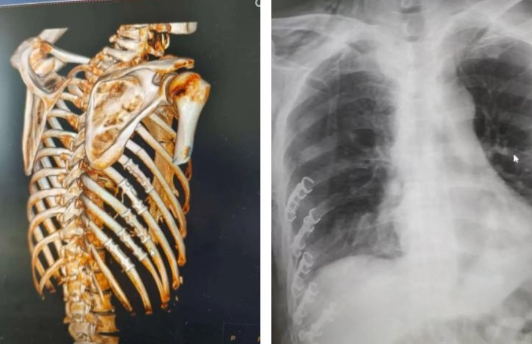

55岁的张先生车祸受伤严重,被紧急送到集团急诊中心救治,经CT检查显示,右侧第4-12肋骨多根多处骨折,右侧气胸、胸腔积液(积血可能),右肺渗出性改变,考虑创伤性湿肺,左肺坠积性改变,气管及左右主支气管痰液潴留,右咽旁、右颈部、胸腰背部、右上肢软组织区广泛积气。查体见连枷胸,反常呼吸,吸氧状态下仍无法维持氧饱和度在正常状态。

胸外科专家团队经过术前讨论一致认为,患者手术风险大,却是其重获生存之机的唯一希望。在麻醉科与ICU的大力协助下,紧密协作,在严格的手术风险评估后,经过团队的不懈努力,充分评估患者的病情后,以微创快速康复理念为原则,制定手术详细方案,讨论手术中的难点和可能出现的问题,并制定好相关应急预案。胸外科团队凭借丰富的手术经验,为患者实施胸腔镜辅助下肋骨骨折内固定术+胸腔探查止血术+肺修补术。术中清理了胸腔积血并止血,复位了插入肺组织的肋骨断端,对5根移位明显的肋骨进行了解剖型钛板内固定术,修补了肺组织损伤。

术后5天CT复查结果满意,肋骨骨折固定可,肺复张良好。